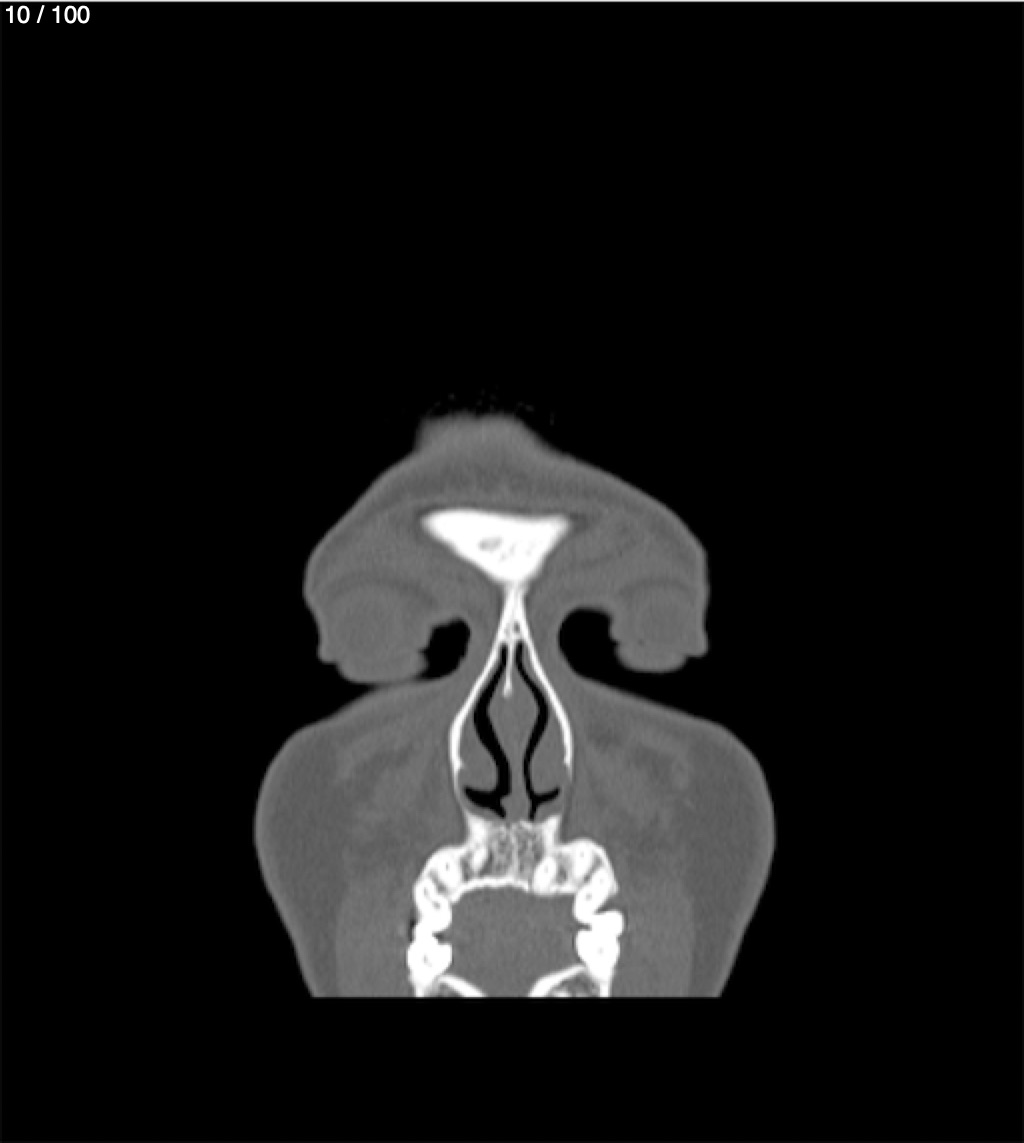

Yonelly Barrios Diaz 35A - T.C Craneo